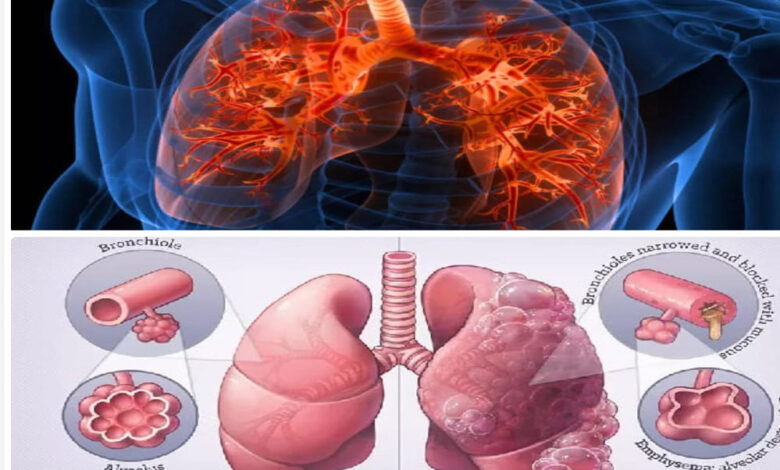

विश्व सीओपीडी दिवस की शुरुआत 2002 में ग्लोबल इनिशिएटिव फॉर क्रॉनिक ऑब्सट्रक्टिव लंग डिजीज (GOLD) द्वारा की गई थी। इस दिवस का मुख्य उद्देश्य सीओपीडी (क्रॉनिक ऑब्सट्रक्टिव पल्मोनरी डिजीज) के प्रति जागरूकता बढ़ाना और इसके रोकथाम, प्रबंधन तथा इलाज को बढ़ावा देना है। यह दिवस हर साल नवंबर के तीसरे बुधवार को मनाया जाता है, और इसका उद्देश्य सरकारों, स्वास्थ्य संगठनों और आम जनता के बीच संवाद स्थापित करना है, ताकि इस बीमारी से होने वाली मृत्यु और पीड़ा को कम किया जा सके। इस दिन विशेष रूप से श्वसन स्वास्थ्य और वायु प्रदूषण जैसे मुद्दों पर ध्यान केंद्रित किया जाता है, जो सीओपीडी के मुख्य कारण हैं।

छत्तीसगढ़, जो अपनी प्राकृतिक संपदा और सांस्कृतिक धरोहर के लिए प्रसिद्ध है, अब स्वास्थ्य सेवाओं के क्षेत्र में भी एक नई पहचान बना रहा है। मुख्यमंत्री विष्णुदेव साय और स्वास्थ्य मंत्री श्याम बिहारी जायसवाल के नेतृत्व में राज्य सरकार ने स्वास्थ्य सेवाओं को सुदृढ़ करने के लिए कई महत्वपूर्ण कदम उठाए हैं। छत्तीसगढ़ में सीओपीडी एक गंभीर स्वास्थ्य समस्या बनी हुई है, जो मुख्य रूप से वायु प्रदूषण, तंबाकू सेवन और परंपरागत चूल्हों के धुएं से उत्पन्न होती है। खासकर राज्य के ग्रामीण और आदिवासी क्षेत्रों में यह समस्या ज्यादा देखी जाती है। एमसीबी जिला जो कोयला खनन और औद्योगिक गतिविधियों के लिए जाना जाता है, प्रदूषण और सांस संबंधी बीमारियों का केंद्र बन चुका है। इन समस्याओं के समाधान के लिए राज्य सरकार ने एक समग्र दृष्टिकोण अपनाया है।